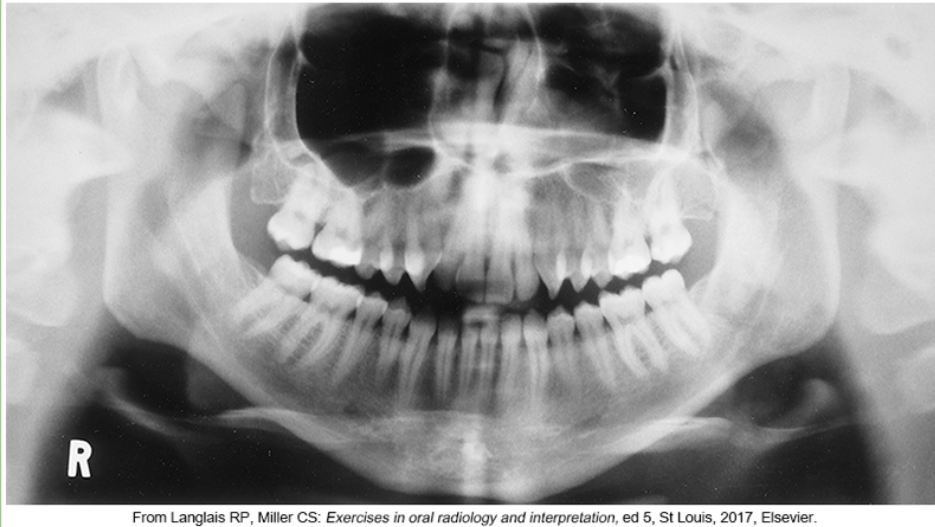

whats the problem

wearing earrings